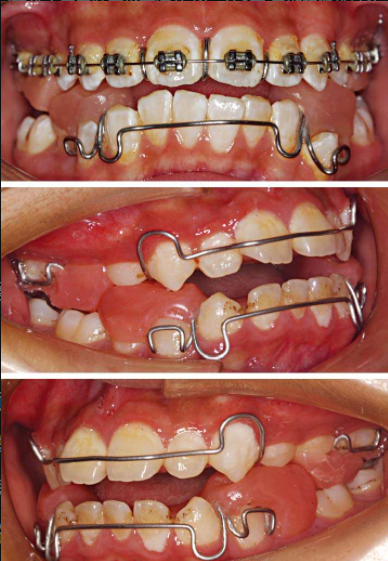

解决方案:粘结式RME配合前方牵引。

图14 RME

图15 粘结式RME

图16 前方牵引

曲断上检查已经有很明显的乳牙Ⅲ、Ⅳ、Ⅴ牙根吸收,口内检查乳牙Ⅲ、Ⅳ、Ⅴ残冠,或者残根。前牙2-2如果尚未萌出,而且估计一年之内不能完全萌出,此时FRⅢ是最好的解决方案,用FRⅢ等待上前牙2-2萌出。如果反𬌗矫治结束后,前牙2-2还没萌出到正常的咬𬌗状态,这时候的反𬌗矫治效果不稳定,很容易复发。矫治后前牙覆𬌗越深,反𬌗矫治效果越稳定。解决方案:肌功能矫治器FRⅢ(图17)。

年轻恒牙列,如果上4已经完全萌出,适合做上颌RPE配合前方牵引。

图18 上颌RPE hyrax扩弓